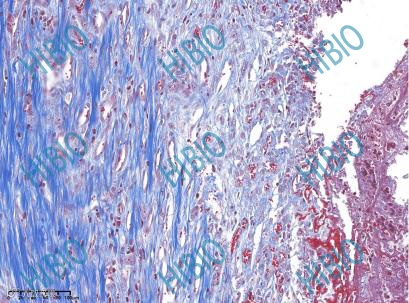

检测指标:动物大体观察、隐静脉HE染色、隐静脉Masson染色、血液学检查。 -

Masson染色图